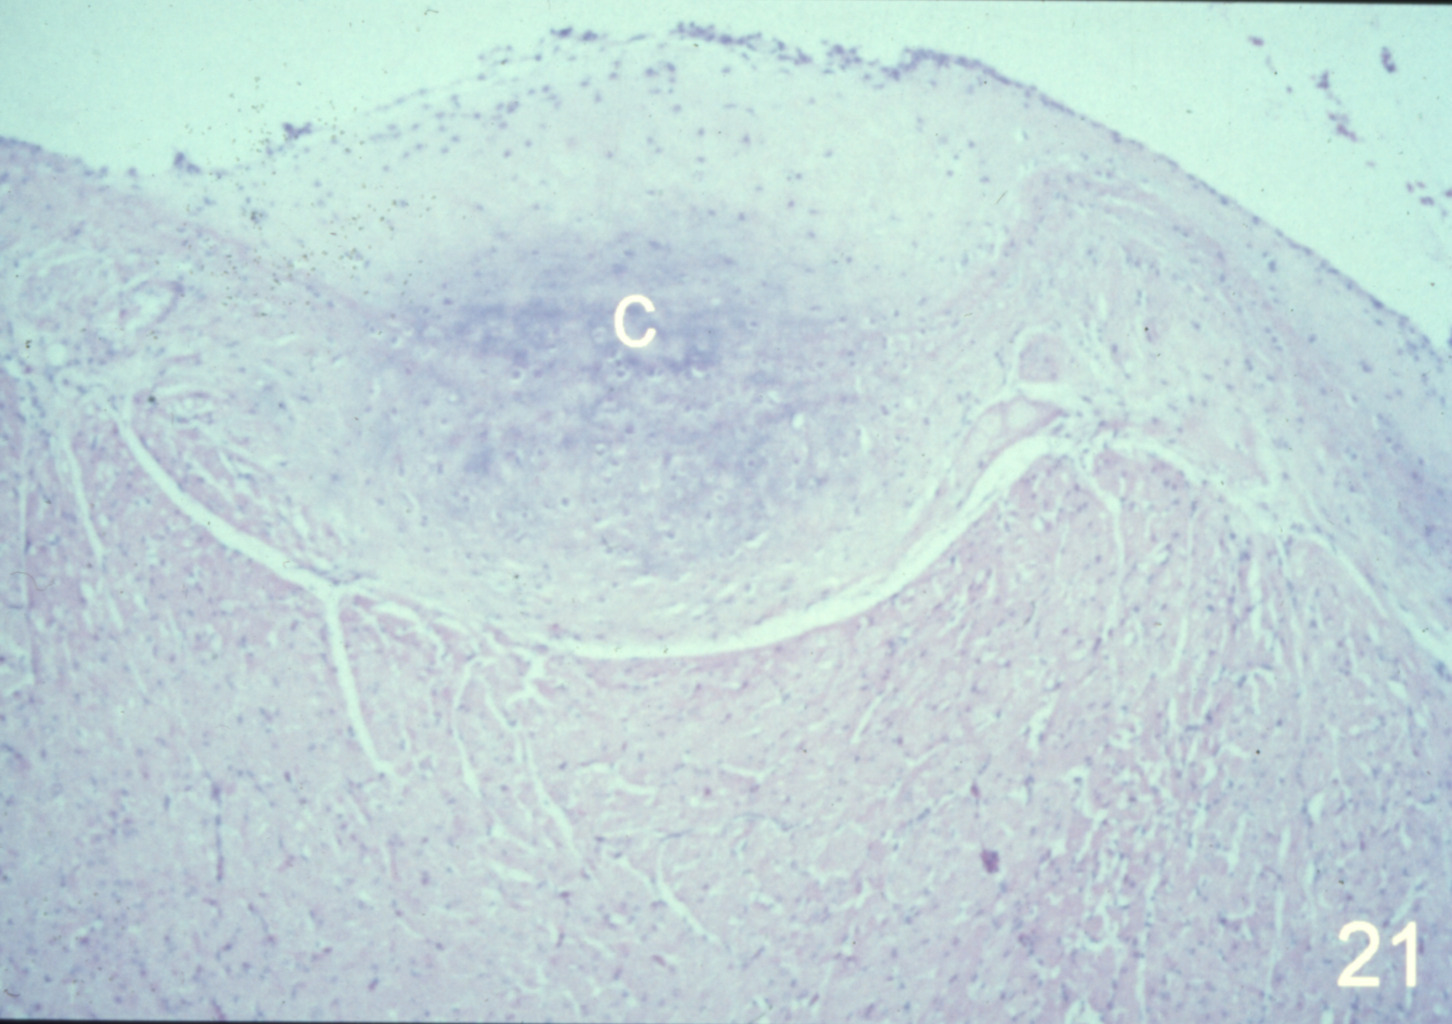

Cardiovascular disease in turkeys (slide study set no. 24)

Turkeys--Diseases Cardiovascular system--Diseases

Slide Study Set #24, Cardiovascular Diseases in Turkeys (includes 27 color slides), 2001